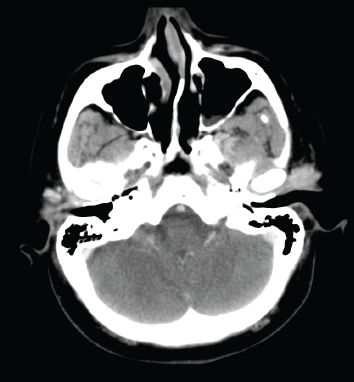

A 61-year-old woman presented four years prior with a painless mass involving the left parotid region. The patient’s medical history was non-contributory. There were no other neurologic signs or symptoms and no history of malignancy. A computed tomography (CT) scan of her head performed four years previously demonstrated an ill-defined lesion in the superficial left parotid gland that corresponded to a palpable preauricular mass (Figure 1). The clinician recommended that this lesion be followed conservatively with observation. However, the lesion gradually increased in size over time. The patient then developed increasing numbness in the left mandibular region, weakness of the ipsilateral frontalis muscle, pain, and left-sided trismus. An ultrasound-guided core biopsy was performed, which demonstrated an intermediate-grade (2/3) ACC. She was then referred to our tertiary oncology centre. Physical examination revealed a firm, tender left parotid mass as well as left Level II adenopathy. There was numbness involving the left V2 and V3 distribution and slight left facial nerve weakness.

Figure 1. A contrast-enhanced axial CT image shows an enhancing, lobulated mass in the left preauricular region.